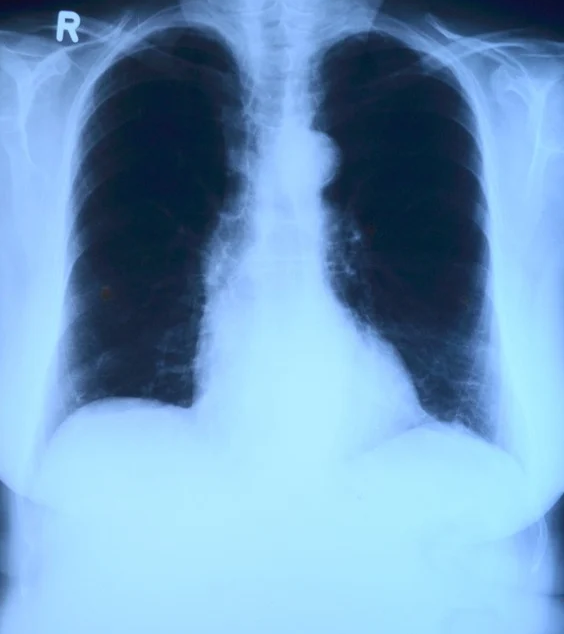

2. 금연 후 신체변화

우리가 흡연을 하게 되면 서서히 건강이 나빠지게 됩니다. 흡연자가 금연을 하더라도 몸이 한 번에 좋아지는 것이 아니라 서서히 좋아지게 되죠. 따라서 금연 후 시간이 지나면서 우리 몸이 어떻게 변화해 가는지 안다면, 금연에 더욱 더 도움이 됩니다. 과연 금연 후 우리 몸에는 어떤 변화가 있을까요?

금연 2~12주 후

- 혈액 순환이 개선되며 폐기능이 향상하게 됩니다.

금연 1~9개월 후

- 기침과 호흡 곤란 증상이 줄어듭니다.

금연 10년 후

- 폐암의 위험성이 흡연자의 절반 수준으로 줄어들게 됩니다.